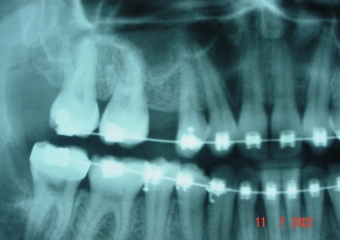

Raio X com Implante Instalado